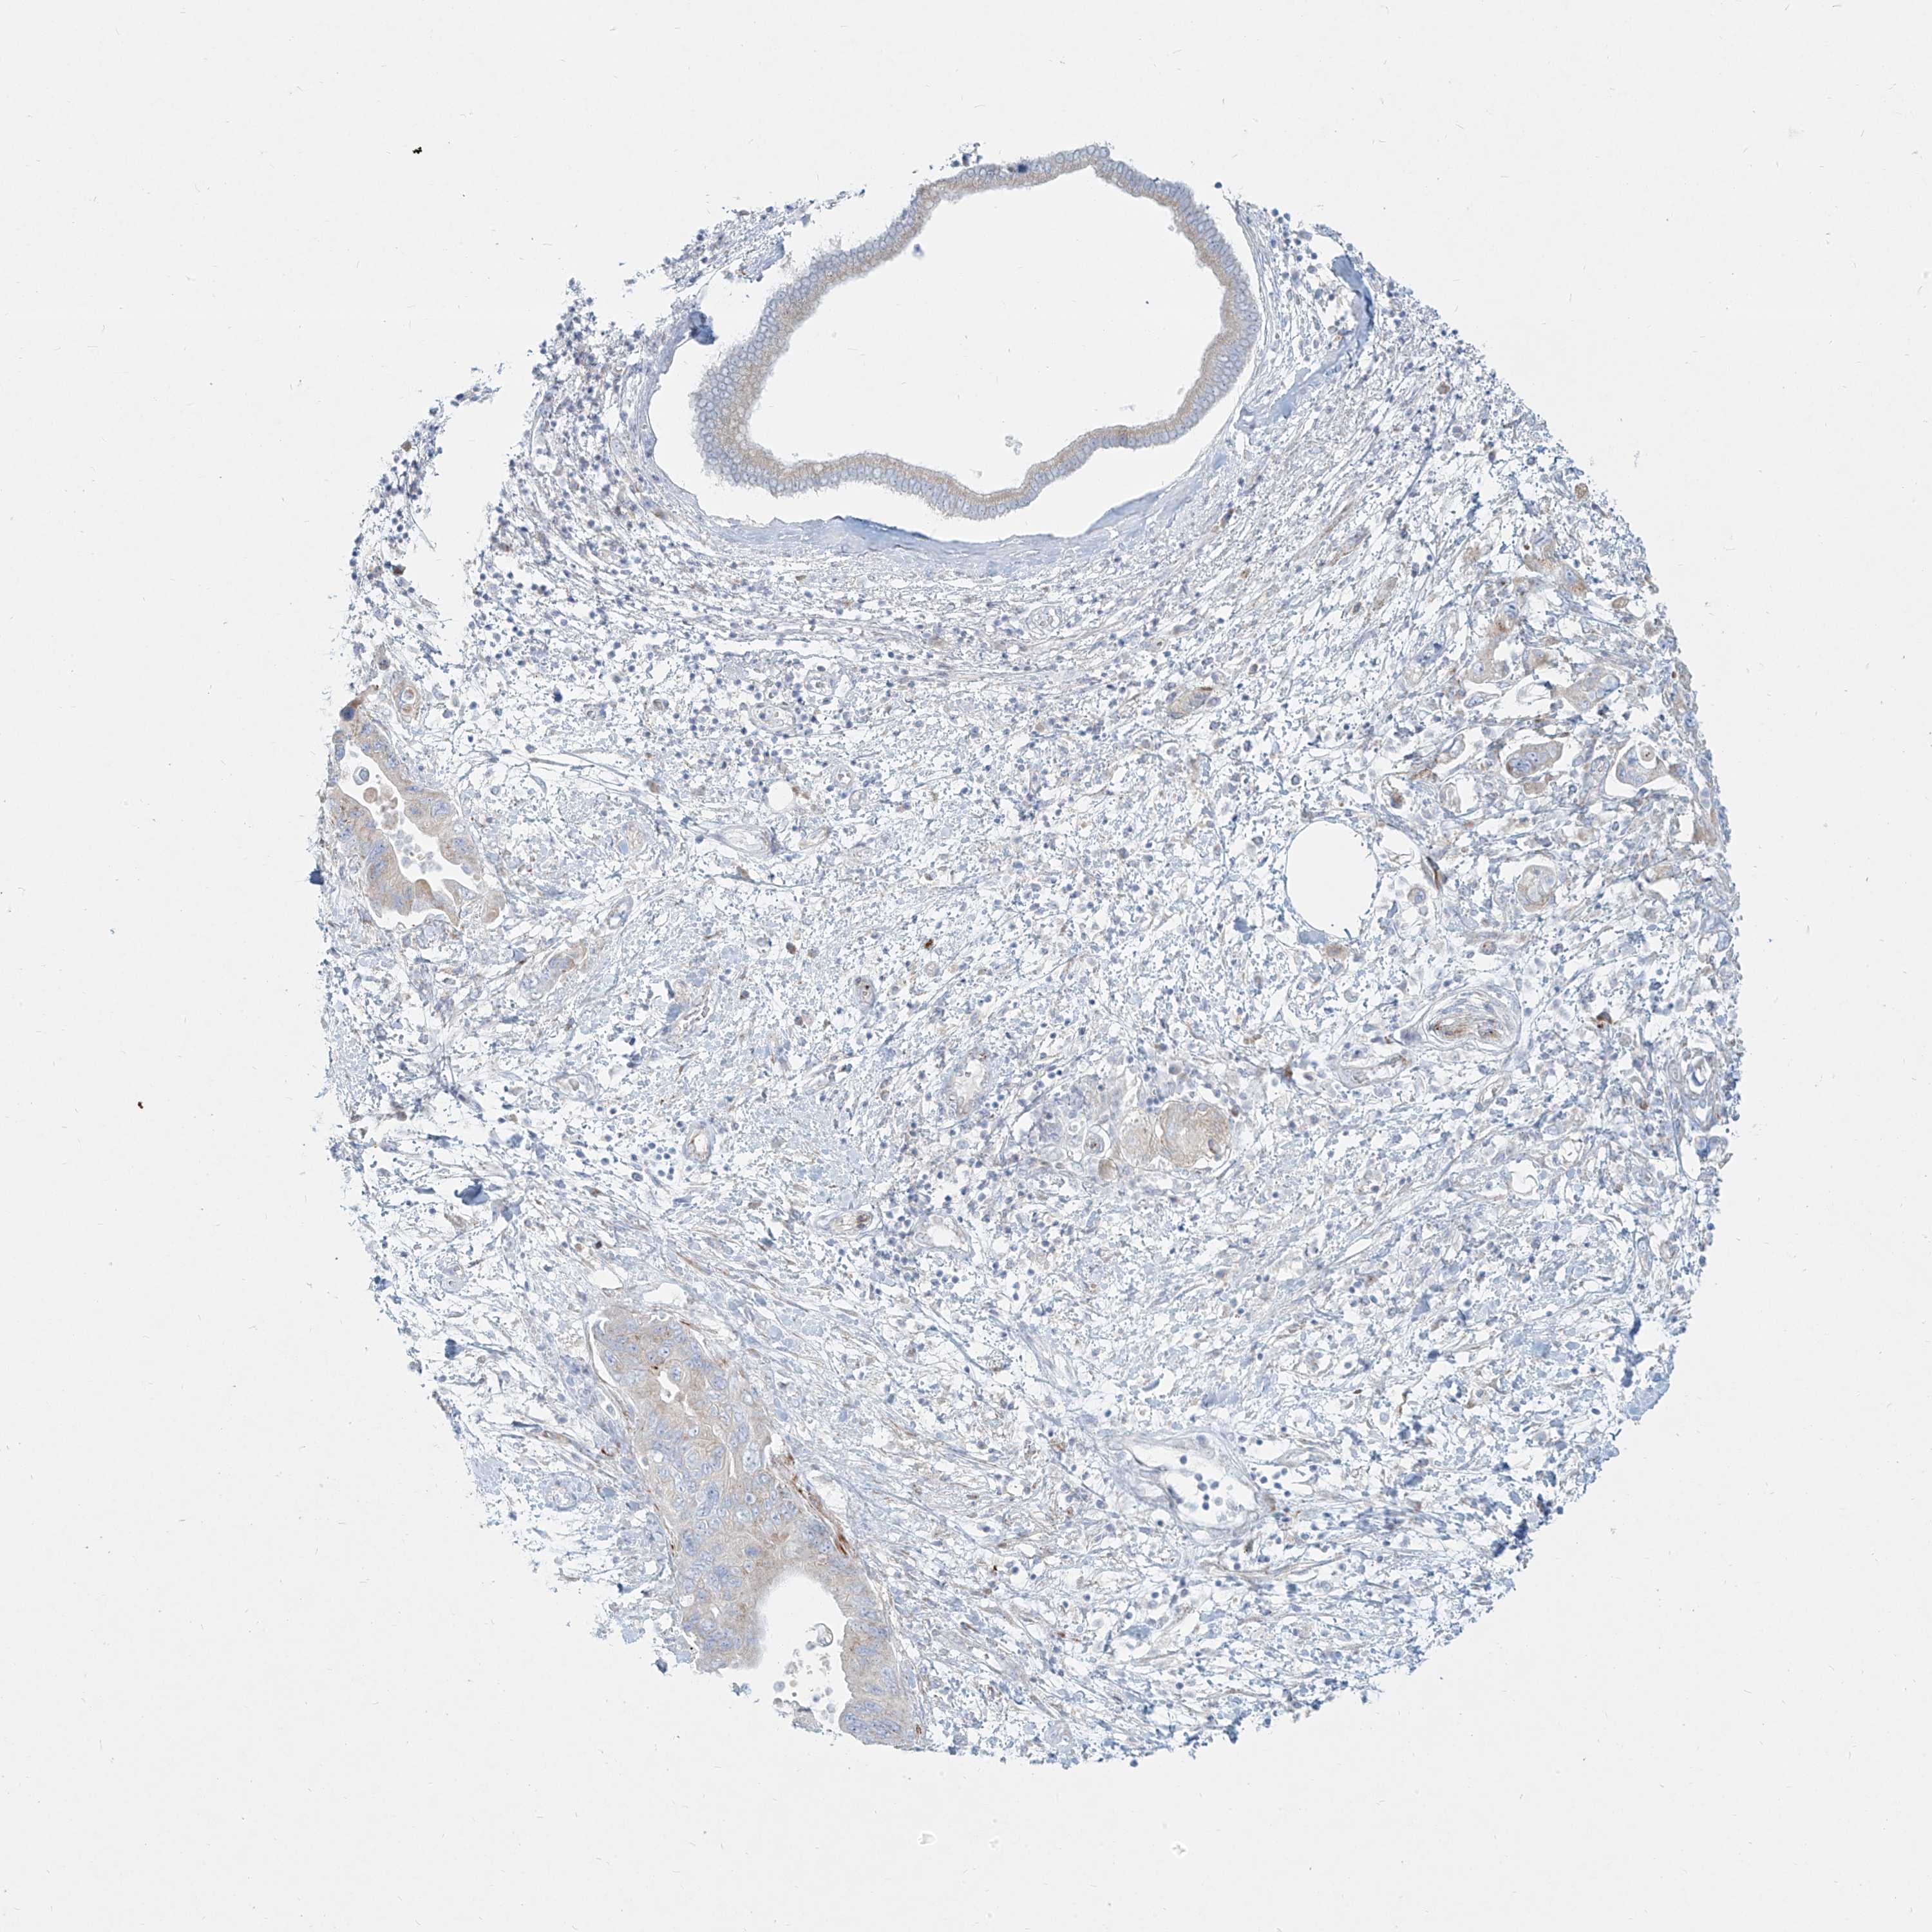

PANCREATIC CANCER - Protein expressioni

A mouse-over function shows sample information and annotation data. Click on an image to view it in a full screen mode. Samples can be filtered based on level of antibody staining by selecting one or several of the following categories: high, medium, low and not detected. The assay and annotation is described here.

Note that samples used for immunohistochemistry by the Human Protein Atlas do not correspond to samples in the TCGA dataset.

Antibody stainingi

Antibody staining in the annotated cell types in the current human tissue is reported as not detected, low, medium, or high, based on conventional immunohistochemistry profiling in selected tissues. This score is based on the combination of the staining intensity and fraction of stained cells.

Each image is clickable and will lead to virtual microscopy that enables deeper exploration of all samples and also displays staining intensity scores, fraction scores and subcellular localization as well as patient and tissue information for each sample.

Antibody HPA031550

Antibody HPA031551

Antibody HPA031552

Staining

High

Medium

Low

Not detected

Intensity

Strong

Moderate

Weak

Negative

Quantity

>75%

75%-25%

<25%

None

Location

Nuclear

Cytoplasmic/membranous

Cytoplasmic/membranous,nuclear

Adenocarcinoma, NOS